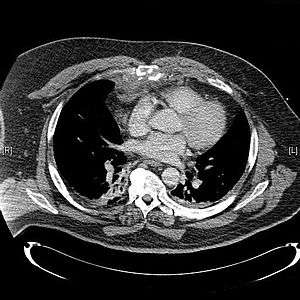

| CT scan showing a comminuted sternal fracture.[1] | |